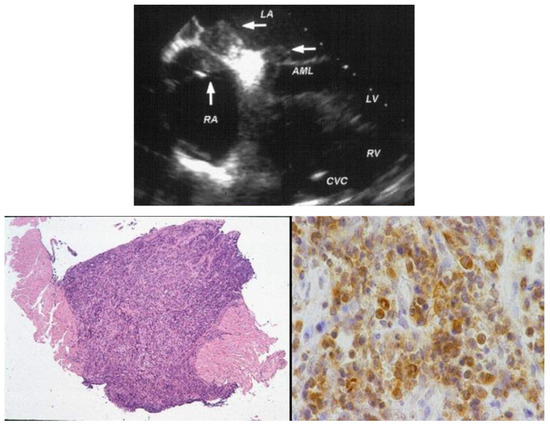

7. Clinical Indications of Endomyocardial Biopsy

- Testolin, L.; Basso, C.; Pittarello, D.; Casarotto, D.; Valente, M. Cardiogenic Shock Due to Metastatic Cardiac Lymphoma: Still a Diagnostic and Therapeutic Challenge. Eur. J. Cardiothorac. Surg. 2001, 19, 365–368. [Google Scholar] [CrossRef]

- Perazzolo Marra, M.; Thiene, G.; Rizzo, S.; De Lazzari, M.; Carturan, E.; Tona, F.; Caforio, A.L.; Cacciavillani, L.; Marcolongo, R.; Tarantini, G.; et al. Cardiac Magnetic Resonance Features of Biopsy-Proven Endomyocardial Diseases. JACC Cardiovasc. Imaging 2014, 7, 309–312. [Google Scholar] [CrossRef]